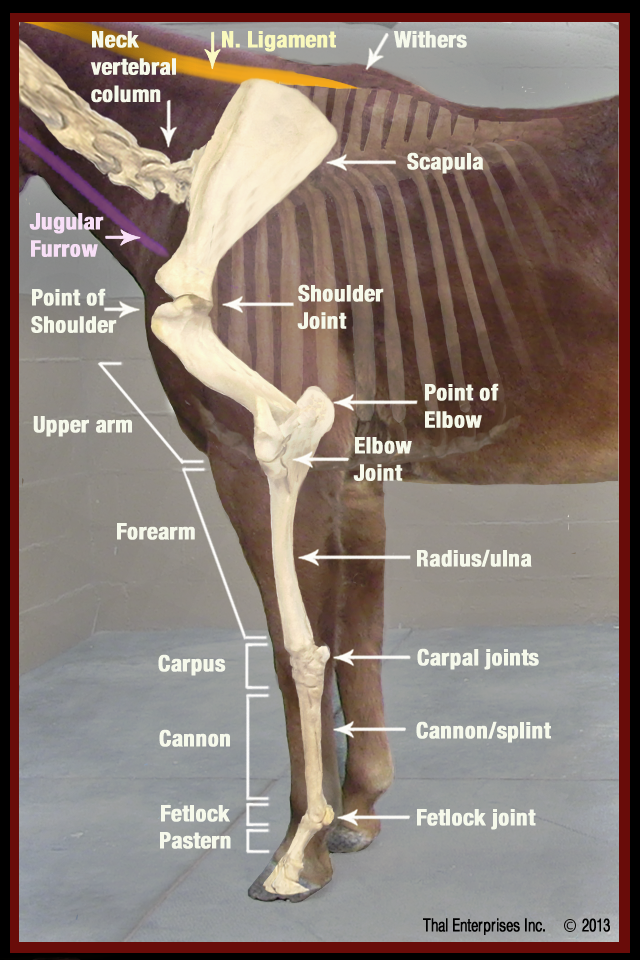

Front Limb

Ön Ayak Topallığı

Görsel Rehber